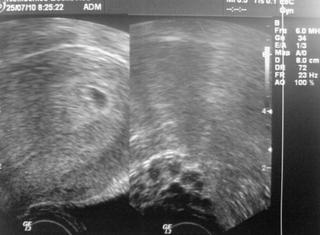

tak su konečně zpět z UTZ,mudr říkal,že vidí náznak srdeční akce,že tak za 2 dny to půjde už vidět zřetelně,že jsem teprve podle UTZ 5tt,nejdýl 29den po ovulaci,takže zřetelné srdíčko tak příští týden..Že to vypadá zatím jako normální standartní vývoj,jen že byla později ovulka,tak se to celé posunulo..oproti minulému týdnu je tam veliký posun,hodně se to zvětšilo..Fotečku nemám ☹